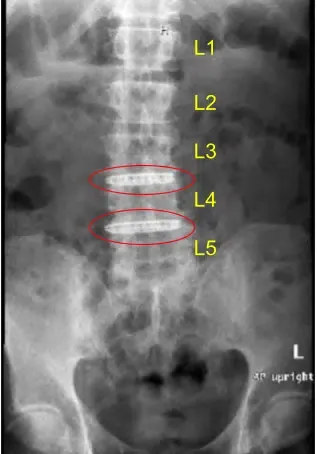

La resonancia magnética y la tomografía computarizada de la columna lumbar mostraron una grave ruptura degenerativa del espacio discal en L3-L4 y L4-L5, por lo que se les ofreció una cirugía para el dolor discogénico. Se explicaron extensamente los riesgos y posibles beneficios de la cirugía al paciente.

El espacio del disco se estrecha en L3-L4 y L4-L5

Protuberancia discal y artropatía facetaria

Firmaron el consentimiento informado y fueron llevados al quirófano para el procedimiento mencionado. Los hallazgos de la radiografía preoperatoria de la columna lumbar se muestran arriba y los pacientes también se sometieron a una tomografía computarizada preoperatoria (TAC) que se muestra arriba.